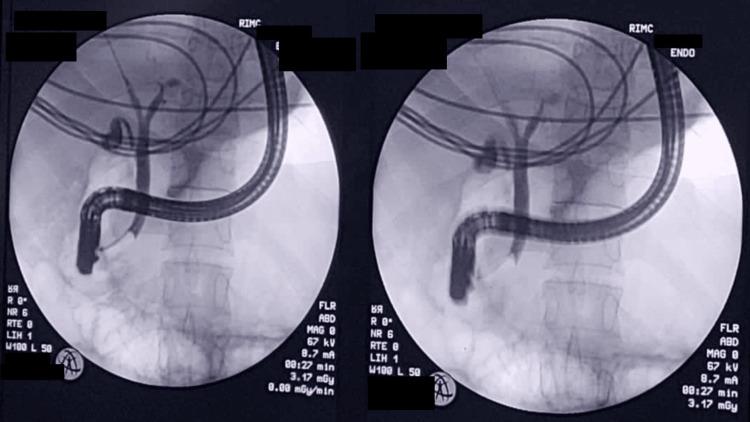

A contracted or "vanishing" gallbladder is a condition characterized by severe atrophy or fibrosis of the gallbladder, often resulting from chronic inflammation, recurrent cholecystitis, gallstone disease, or metabolic disorders such as diabetes and chronic alcohol use. The etiopathogenesis involves progressive fibrosis due to persistent biliary obstruction, chronic infection, or impaired blood flow, particularly in patients with liver cirrhosis. While the exact incidence remains unclear, it is more prevalent in individuals with long-standing hepatobiliary diseases or metabolic syndromes. Common symptoms include severe right upper quadrant pain, jaundice, nausea, vomiting, and signs of obstructive jaundice, such as dark urine and pale stools. Diagnostic investigations typically involve ultrasound, contrast-enhanced computed tomography (CECT), magnetic resonance cholangiopancreatography (MRCP), and endoscopic retrograde cholangiopancreatography (ERCP) to assess biliary obstruction, liver pathology, and gallbladder morphology. Treatment requires a multidisciplinary approach, including initial ERCP for biliary decompression, followed by surgical intervention (laparoscopic or open cholecystectomy), with conversion to open surgery often necessary due to dense adhesions and fibrosis. Postoperative care focuses on managing comorbidities, preventing complications, and long-term monitoring of liver health. This case report presents the challenging management of a 34-year-old male with a history of diabetes mellitus, chronic alcohol use, and liver cirrhosis, who presented with severe right upper quadrant pain, jaundice, and ascites. Initial evaluation revealed cholangitis, calculous cholecystitis with choledocholithiasis, and imaging findings consistent with liver cirrhosis. The patient underwent ERCP for biliary stenting and sludge extraction, followed by an attempted laparoscopic cholecystectomy. Intraoperatively, dense adhesions and fibrosis obscured the gallbladder, confirming a contracted or "vanishing" gallbladder, prompting conversion to an open procedure. The case highlights the diagnostic complexities of contracted gallbladders, which often result from chronic inflammation, fibrosis, or metabolic disorders. Preoperative imaging, including ultrasound and MRCP, played a critical role in identifying biliary obstruction and liver pathology. However, intraoperative findings necessitated adaptive surgical decision-making to mitigate risks such as bile duct injury or hemorrhage. The patient's multiple comorbidities further complicated management, emphasizing the need for a multidisciplinary approach involving gastroenterologists, surgeons, and hepatologists. Postoperative recovery was closely monitored for complications, including infection and bile leaks. The patient was discharged with follow-up care focusing on liver health, diabetes management, and alcohol cessation. This report underscores the importance of thorough preoperative assessment, flexibility in surgical technique, and collaborative care in optimizing outcomes for patients with complex gallbladder pathology. Future research should explore long-term outcomes and improved imaging techniques to enhance surgical planning for such challenging cases.

胆囊萎缩或“消失”是一种以胆囊严重萎缩或纤维化为特征的病症,通常由慢性炎症、复发性胆囊炎、胆结石病或代谢紊乱(如糖尿病和长期酗酒)引起。其发病机制涉及由于持续性胆管梗阻、慢性感染或血流受损导致的进行性纤维化,在肝硬化患者中尤为常见。虽然确切发病率尚不清楚,但在患有长期肝胆疾病或代谢综合征的个体中更为普遍。常见症状包括右上腹剧痛、黄疸、恶心、呕吐以及梗阻性黄疸的体征,如尿色深和大便色浅。诊断性检查通常包括超声、增强计算机断层扫描(CECT)、磁共振胆胰管造影(MRCP)和内镜逆行胆胰管造影(ERCP),以评估胆管梗阻、肝脏病理和胆囊形态。治疗需要多学科方法,包括首先进行ERCP以解除胆管梗阻,随后进行手术干预(腹腔镜或开腹胆囊切除术),由于致密粘连和纤维化,通常需要转为开腹手术。术后护理重点在于管理合并症、预防并发症以及对肝脏健康进行长期监测。本病例报告介绍了一名34岁男性患者的具有挑战性的治疗过程,该患者有糖尿病、长期酗酒和肝硬化病史,出现右上腹剧痛、黄疸和腹水。初步评估显示胆管炎、结石性胆囊炎伴胆总管结石,影像学检查结果与肝硬化相符。患者接受了ERCP胆管支架置入和胆泥清除,随后尝试进行腹腔镜胆囊切除术。术中,致密粘连和纤维化使胆囊难以辨认,证实为萎缩或“消失”的胆囊,促使手术转为开腹手术。该病例突出了萎缩性胆囊的诊断复杂性,这通常由慢性炎症、纤维化或代谢紊乱引起。术前影像学检查,包括超声和MRCP,在识别胆管梗阻和肝脏病理方面发挥了关键作用。然而,术中发现需要灵活的手术决策以降低胆管损伤或出血等风险。患者的多种合并症使治疗更加复杂,强调了需要胃肠病学家、外科医生和肝病学家参与的多学科方法。术后密切监测恢复情况以预防并发症,包括感染和胆漏。患者出院时接受以肝脏健康、糖尿病管理和戒酒为重点的随访护理。本报告强调了全面术前评估、手术技术灵活性以及协作护理对于优化复杂胆囊病理患者治疗效果的重要性。未来研究应探索长期预后以及改进成像技术,以加强对此类具有挑战性病例的手术规划。